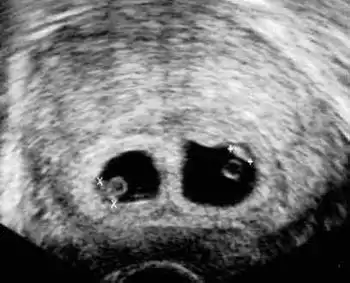

С появлением ультразвука врачи научились "устанавливать" количество детей в утробе мамы на самых ранних сроках. Перед вами - классическая двойня...